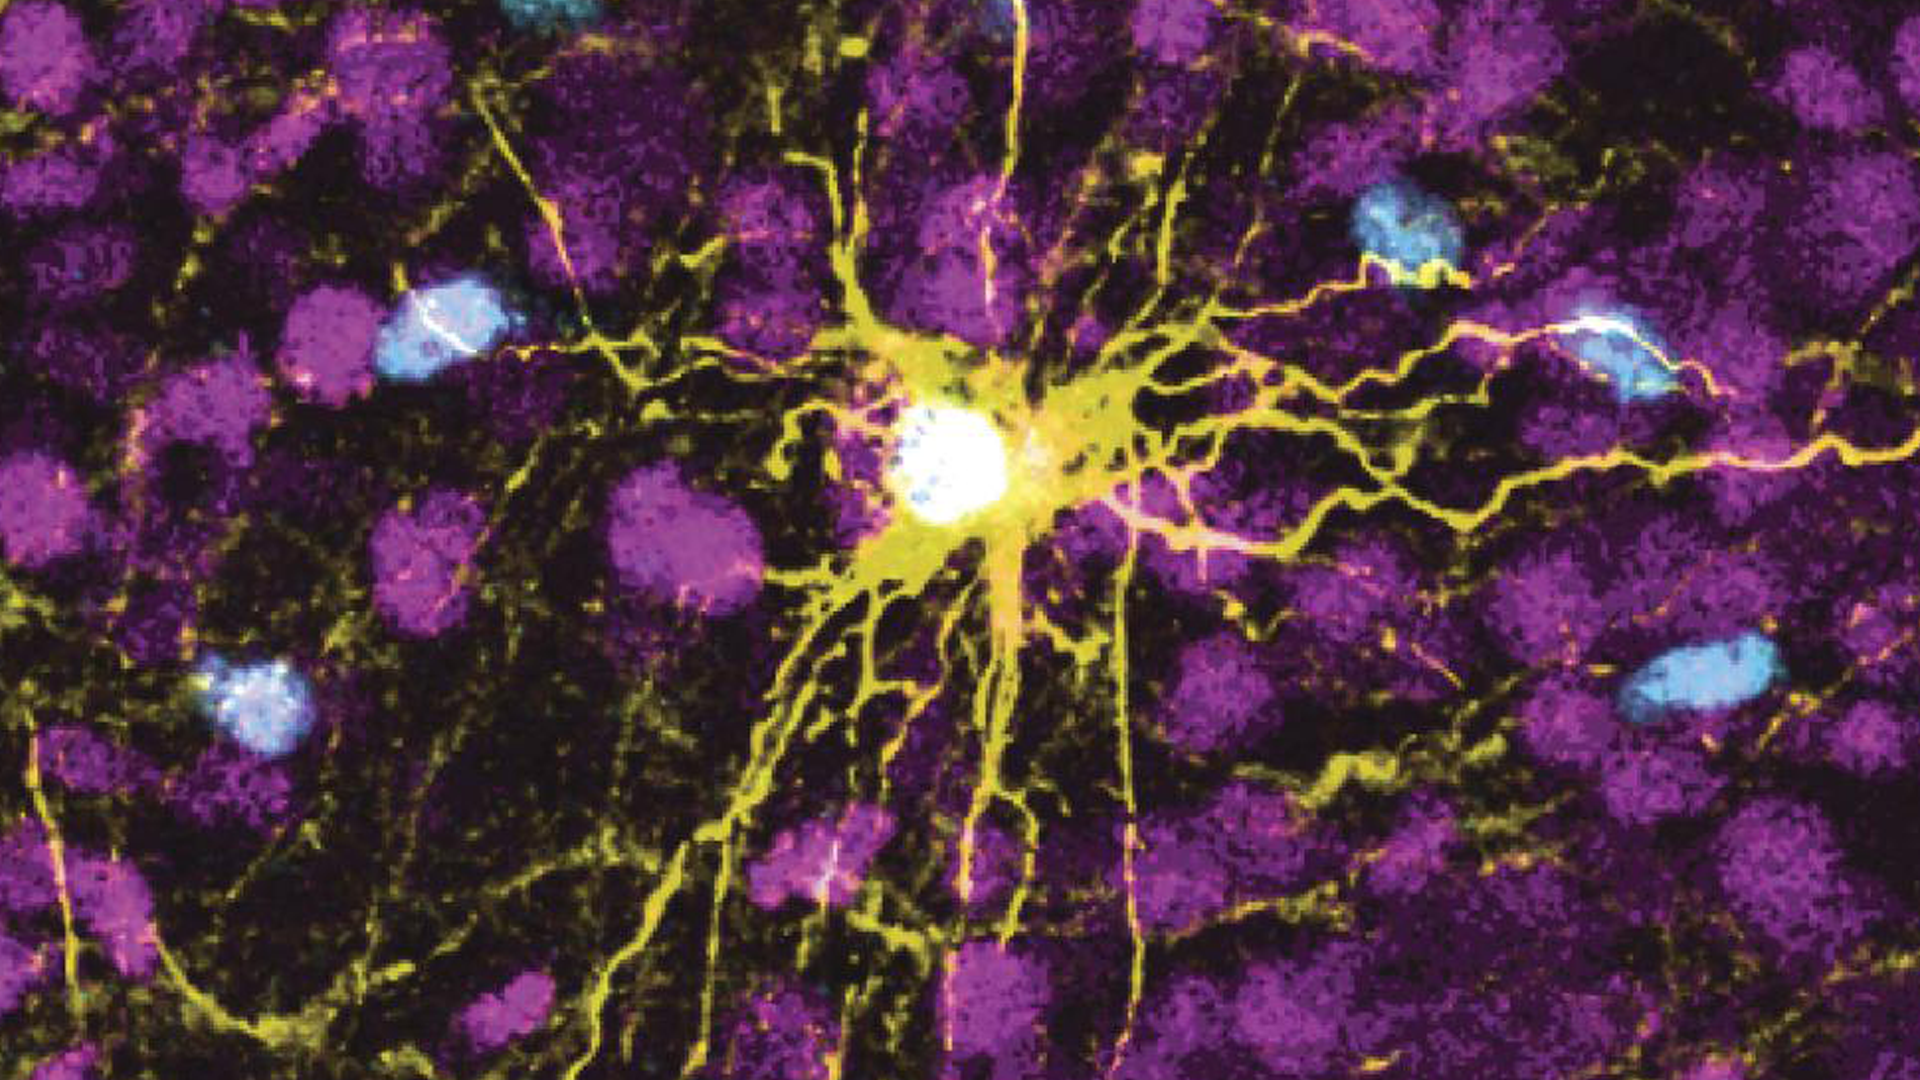

To make the brain organoids, Stanford University scientists transformed human skin cells into stem cells and then coaxed them to become several types of brain cells. Those cells then multiplied to form organoids resembling the cerebral cortex, the human brain’s outermost layer, which plays a key role in things like memory, thinking, learning, reasoning and emotions.

Scientists transplanted those organoids into rat pups 2 to 3 days old, a stage when brain connections are still forming. The organoids grew so that they eventually occupied a third of the hemisphere of the rat’s brain where they were implanted. Neurons from the organoids formed working connections with circuits in the brain.

Human neurons have been transplanted in rodents before, but generally in adult animals, usually mice. Pasca, a psychiatry professor at the Stanford School of Medicine, said this is the first time these organoids have been placed into early rat brains, creating “the most advanced human brain circuitry ever built from human skin cells and a demonstration that implanted human neurons can influence an animal’s behavior.”